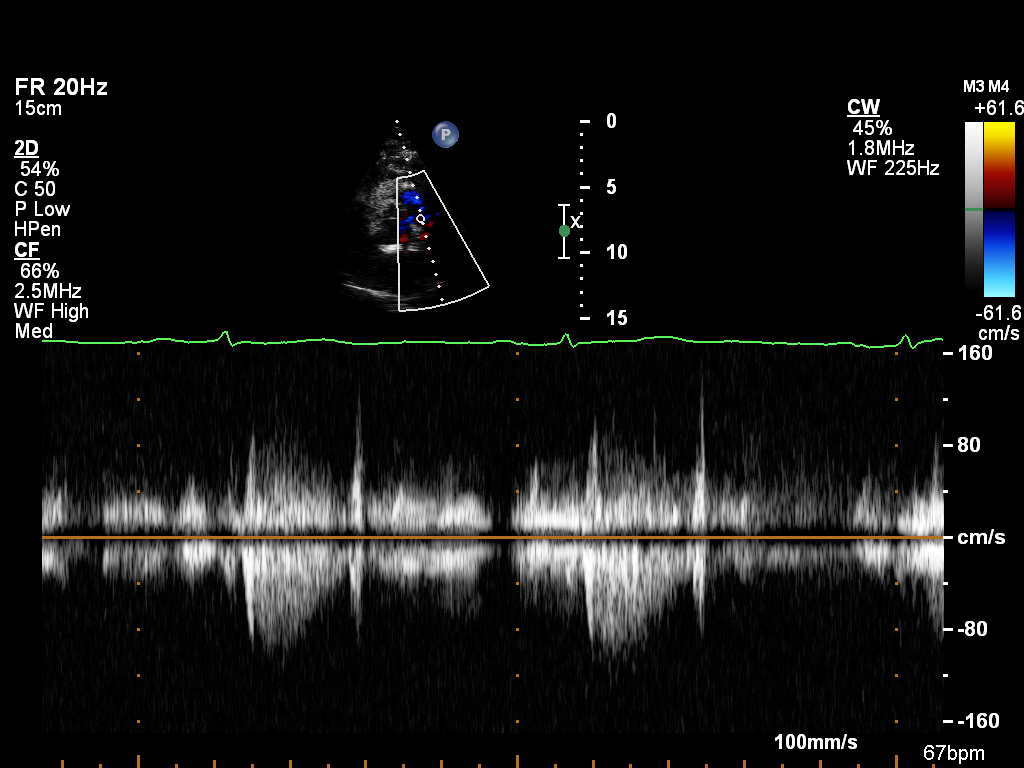

Doppler (8 views)

ImageView NameDescription

doppler-ao doppler-ao Spectral Doppler of the descending aorta

doppler-av doppler-av Spectral Doppler of the aortic valve

doppler-mv doppler-mv Spectral Doppler of the mitral valve

doppler-pv doppler-pv Spectral Doppler of the pulmonary valve

doppler-tv doppler-tv Spectral Doppler of the tricuspid valve